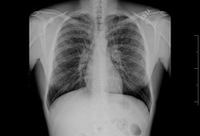

Bronquiectasia

Radiografia torácica com vias aéreas dilatadas e espessadas

Dos arquivos do Dr. Sangeeta M. Bhorade; uso autorizado